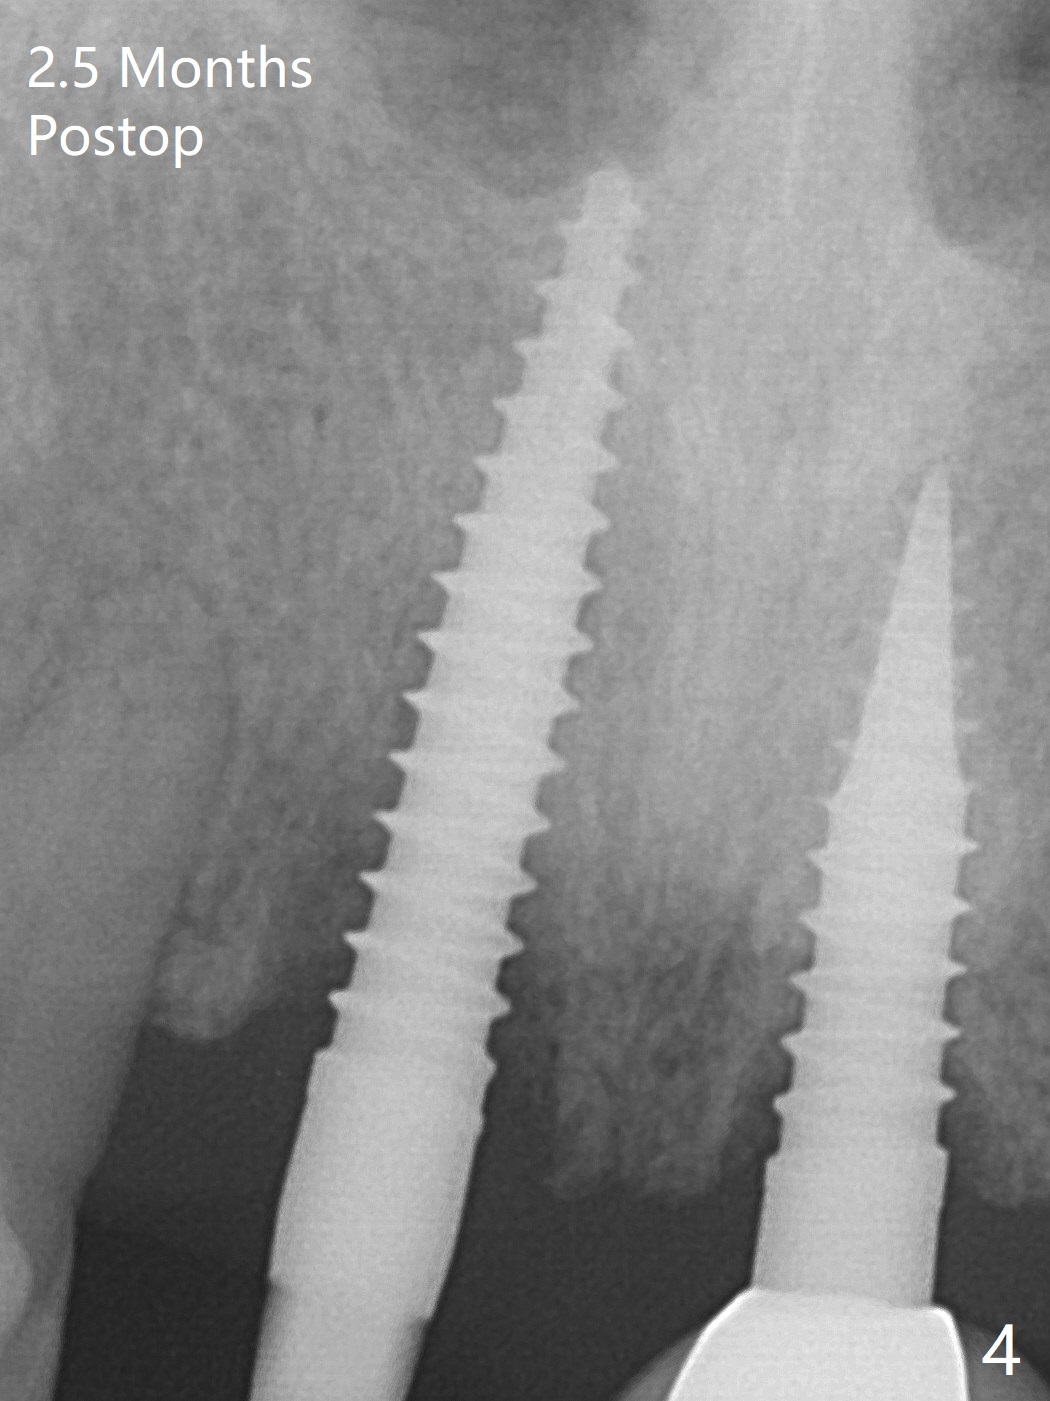

Reanalysis of preop CBCT shows a longer implant (3x16mm, green) to be placed palatal should be able to solve buccal plate bone loss associated with the previous 3x14 mm one at #8 (Fig.1). After crown/implant removal (with ease), a new palatal osteotomy is initiated flapless with 1.2 mm drill for 16 mm (palatal gingival margin, Fig.2). Following 1.5 mm drill for ~ 17 mm, a 3x16(2) mm 1-piece implant is placed >40 Ncm (Fig.3). After bone graft through limited access and abutment preparation, an immediate provisional is fabricated with clearance. The provisional dislodges repeatedly, mainly due to palatal perforation. It gets lost while the patient travels to his home country. Although there seems to be bone loss around the implant 2.5 months postop (Fig.4), the gingiva looks healthy. A new provisional is fabricated without impression. Because of short vertical height and small abutment diameter as well as bruxism, the provisional easily dislodges. The patient will return for impression 4 months 10 days postop. The bone loss remains 4 months postop when impression is taken (Fig.5).